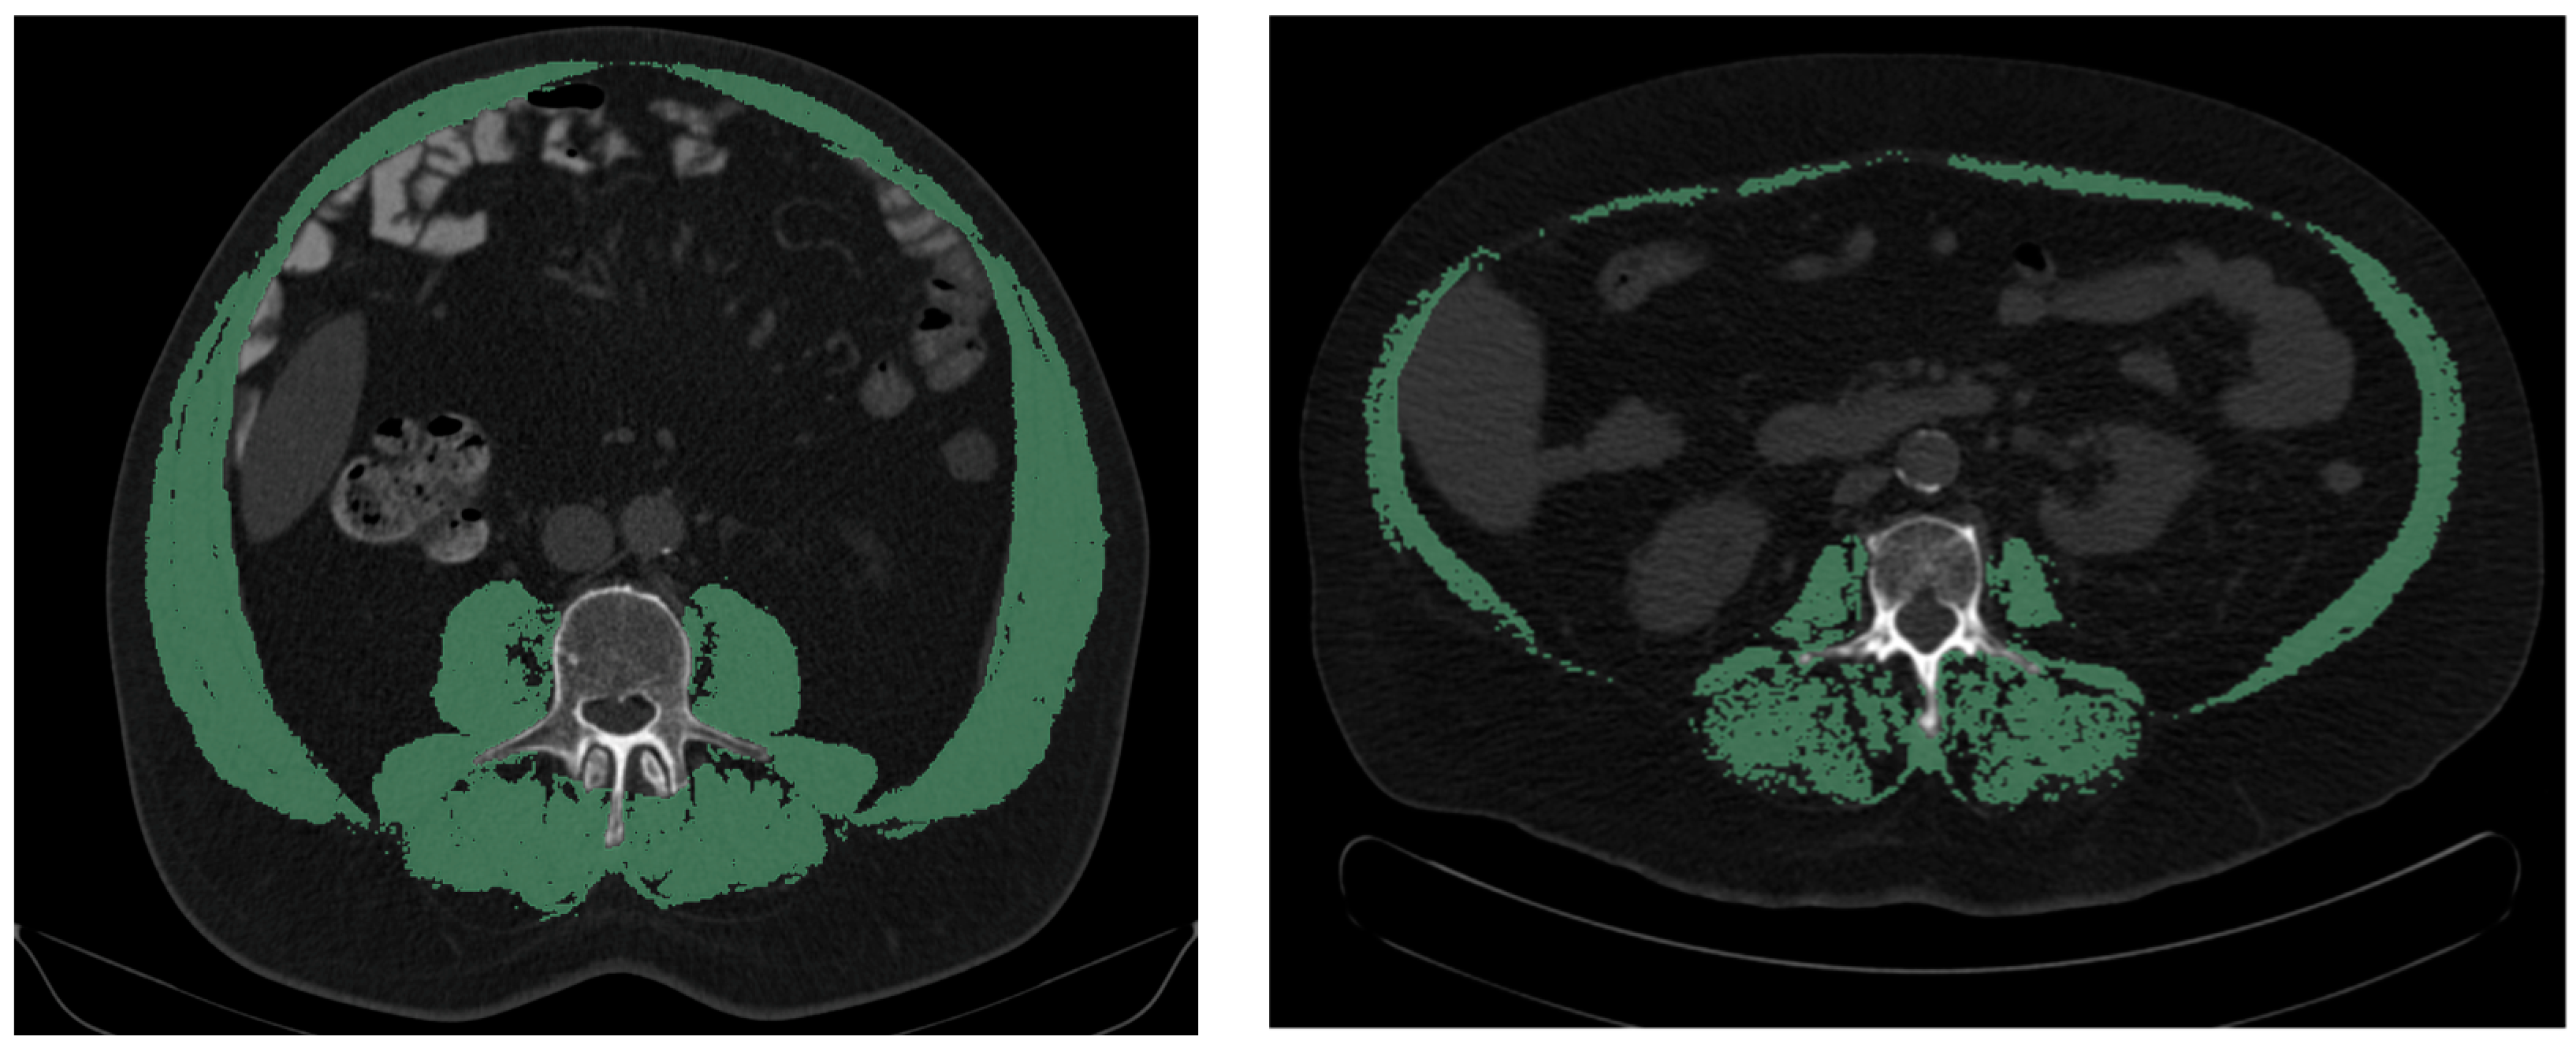

4. Discussion